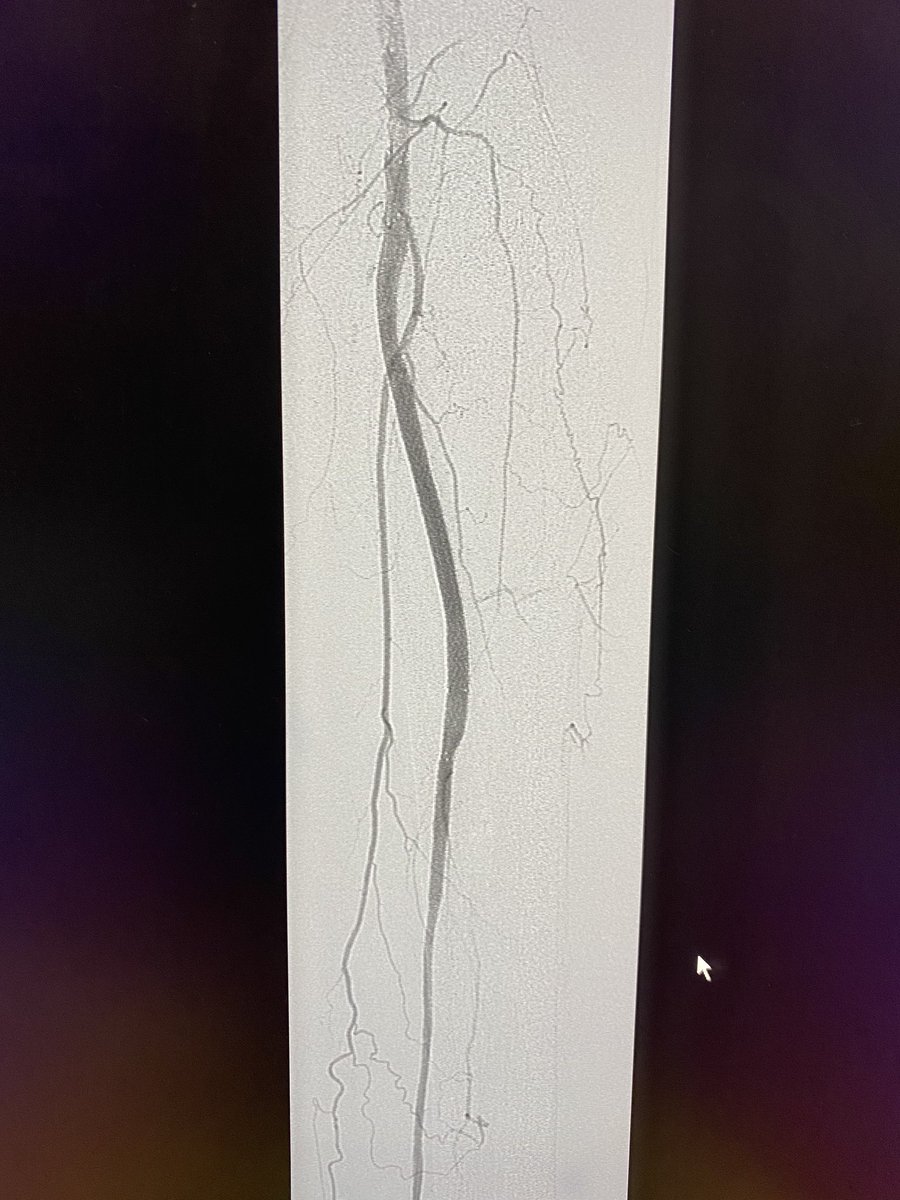

Transradial Infrapopliteal Atherectomy, Angioplasty and Stenting for Cri... youtu.be/Gf8tdMXcBls via @YouTube